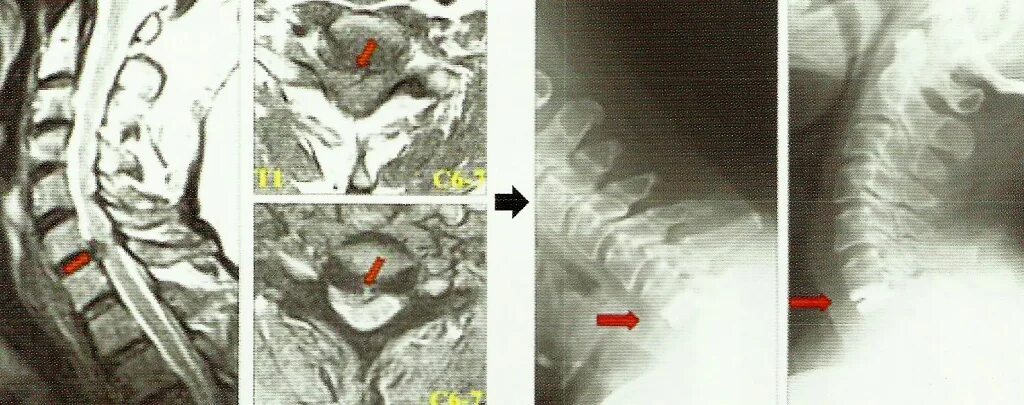

Грыжа в шее форум